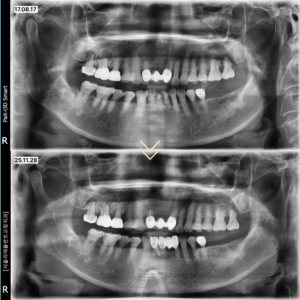

고령의 환자였기 때문에 신경치료와

치근단절제술을 한 번에 진행하지 않고

약 한 달 정도의 시간을 두어

단계적으로 치료를 시행하였습니다.

신경치료 후 염증의 범위가 안정된 것을 확인한 뒤

치근단절제술을 통해 잔존해 있던

염증 조직을 완전히 제거하였습니다.

치료 결과

전치부의 치근단농양은 완벽하게 제거되었고

손실되었던 치조골 역시 시간이 지나면서

100%에 가까운 재생이 관찰되었습니다.

집중치료기간은 약 2달로 이후 1년뒤에도

보존이 잘 이루어지고 있음을 확인할 수 있습니다.